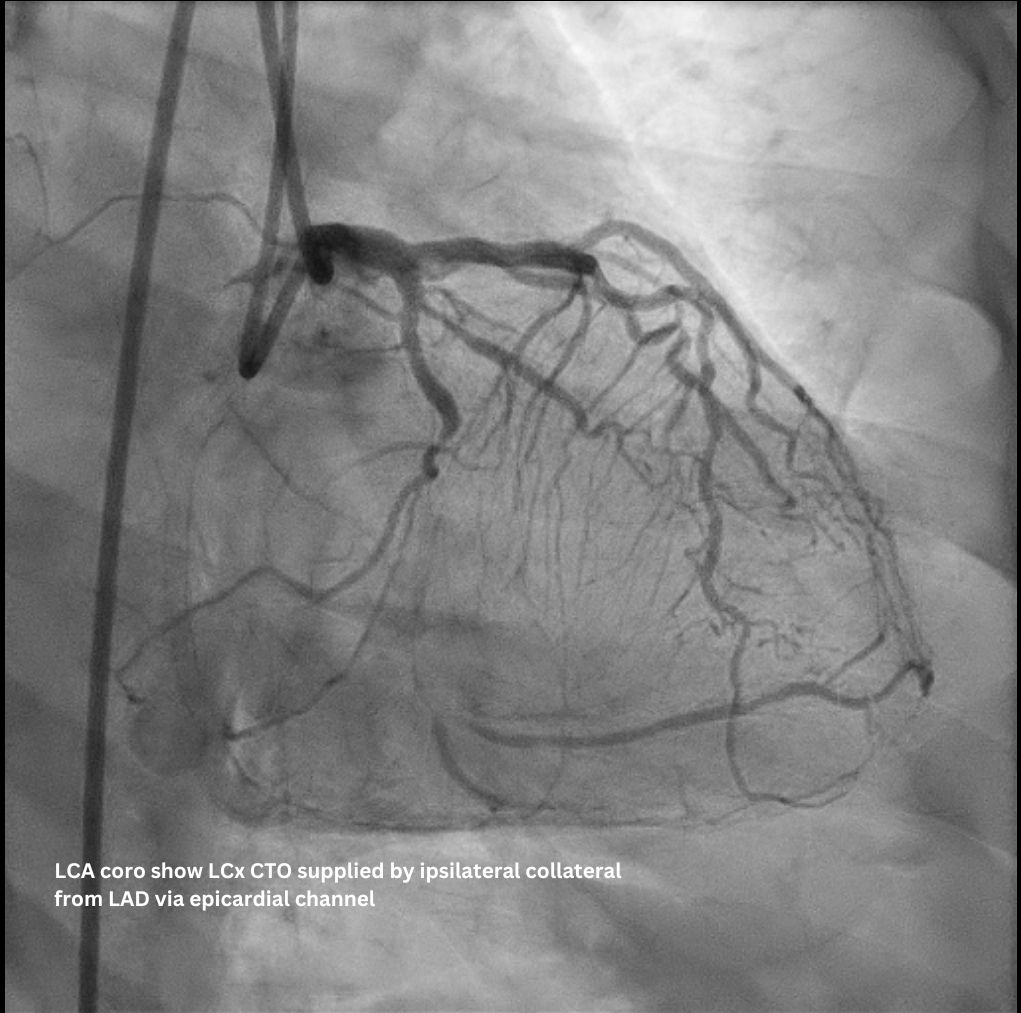

The staged PCI for the RCA CTO was completed uneventfully via an antegrade approach. Subsequent LCA angiogram showed a p-d LCx CTO supplied by an ipsilateral collateral from the D1/ LAD via an epicardial channel. RCA angiography confirmed no interventional contralateral supply. Detailed lesion analysis showed an ambiguous proximal cap (with the atrial branch as a large side branch), ~20 mm CTO length, a bend > 45¡Æ, and the distal cap located precisely at the dLCx/OM2 bifurcation.

Access was achieved via RRA and US-guided RFA puncture. A 7F SBP 3.5 guide was engaged to LM, and a 6F IL 3.5 guide was in oRCA, confirming no contralateral supply to LCx CTO. After a failed antegrade IVUS guided puncture by GW Gaia Next 2, the strategy shifted retrograde. GW Sion supported by microcatheter Caravel successfully navigated D1 across LAD stent struts, visualizing the ipsilateral epicardial collateral to OM2. The wire was exchanged to SUOH 03 and then advanced to OM2. After initial retrograde wiring failures by a UB3, a Gladius MG successfully crossed the CTO body to pLCx. IVUS to pLCx confirmed retrograde wire in subintimal plane. Multiple attempts R-CART failed in p-mLCx despite wire escalation to GW Gaia Next 3. Repeat IVUS showed enlarging pLCx hematoma, necessitating deployment of a DES (ULTIMASTER NAGOMI 3.0 mm/18 mm) to seal the entry point. Successful stent based R-CART was then achieved with Gaia Next 3, confirmed by IVUS. The IL 3.5 guide was moved to LM as an antegrade Ping-Pong guide for RG3 externalization after successfully advancing retrograde wire and microcatheter to the IL guide. The m-dLCx was prepared by SC balloons and a DES (ULTIMASTER NAGOMI 2.5 mm/50 mm) was deployed to the p-dLCx-OM2, overlapping the proximal DES. A D1 perforation was noted and then successfully treated with fat embolism via the retrograde microcatheter. Final angiogram and IVUS confirmed optimal results.